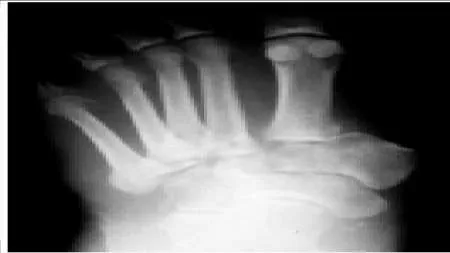

Question 33:

The patient presented (Slide 1 and Slide 2) has a hereditary sensory motor neuropathy. Based upon the photographs, a surgeon should be able to determine the pattern of muscle weakness. Weakness in which muscle is most likely the cause of this deformity:

Correct Answer: Peroneus brevis

Explanation:

Although the anterior tibial muscle is weak, the cavus is the predominant deformity of this condition, caused by weakness of the peroneus brevis. The peroneus longus is functioning and is responsible for the plantarflexion of the first metatarsal.

Question 34:

You are planning a tendon transfer to help correct deformity in a patient with hereditary sensory motor neuropathy. Which of the following muscles will be used for the transfer based upon the clinical appearance of the foot (Slide 1 and Slide 2):

Correct Answer: Posterior tibial

The posterior tibial tendon transfer is a commonly performed surgery for correction of cavus foot deformity associated with weakness of the anterior tibial muscle and varying degrees of drop foot deformity. The removal of the force of the posterior tibial tendon adds to the correction of the deformity of the foot by balancing the absent peroneus brevis. Although the extensor hallucis longus can be used as a tendon transfer, it will not be the primary muscle used or sufficient to correct deformity.